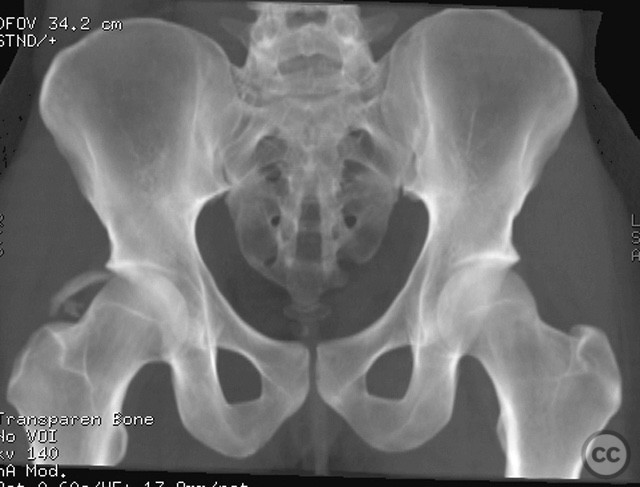

Pelvic Ring - AO/OTA 61x

Pelvis - AO/OTA 6x